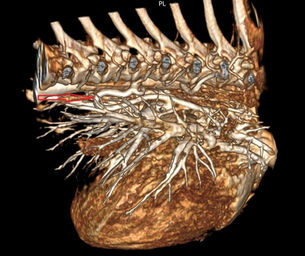

render 1